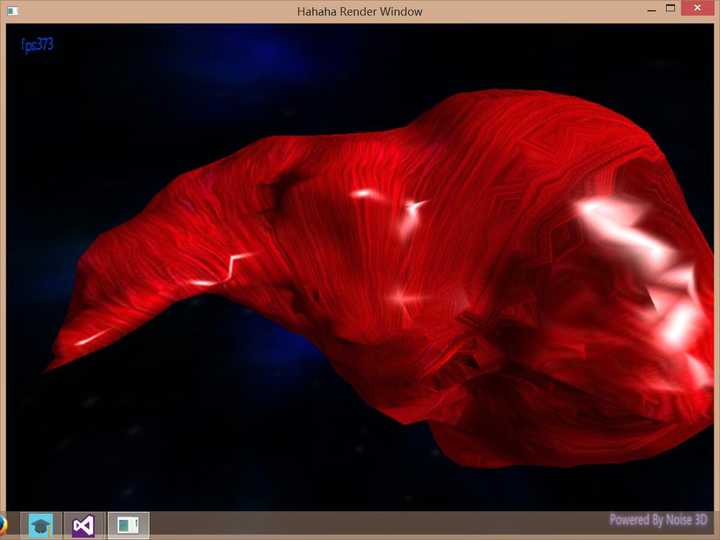

所以最后折衷一下做个网格简化吧!

好多了好多了!